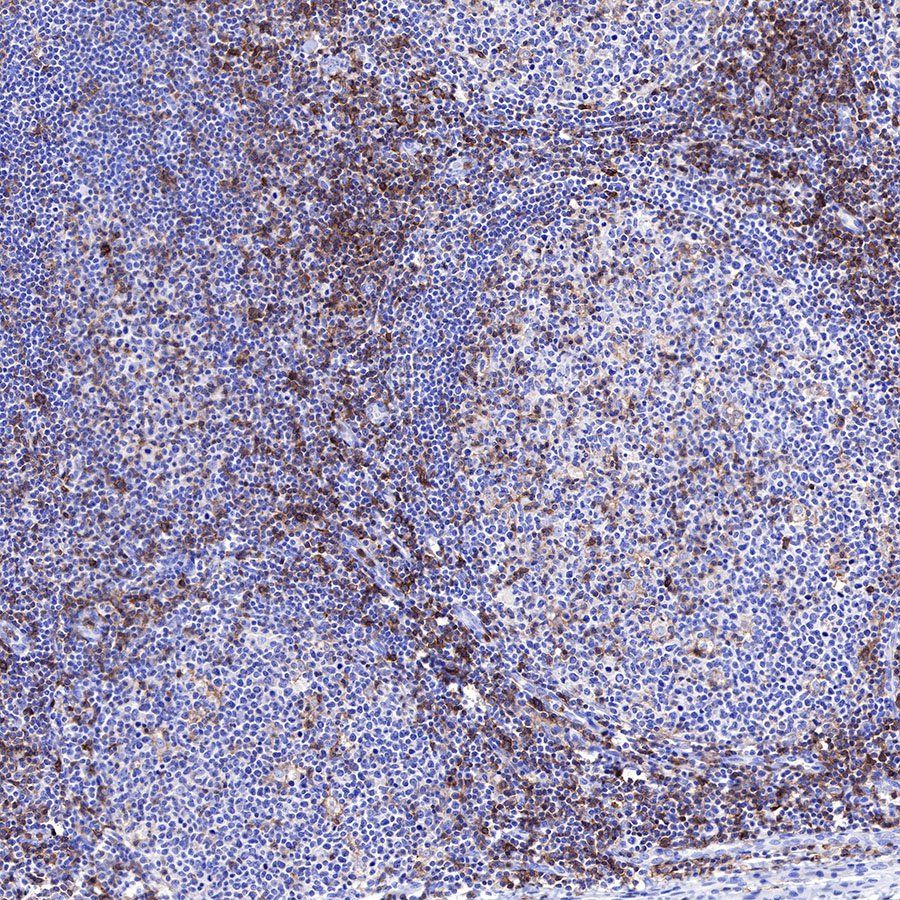

IHC shows positive staining in paraffin-embedded human tonsil. Anti-CD43 antibody was used at 1/1000 dilution, followed by a HRP Polymer for Mouse & Rabbit IgG (ready to use). Counterstained with hematoxylin. Heat mediated antigen retrieval with Tris/EDTA buffer pH9.0 was performed before commencing with IHC staining protocol.